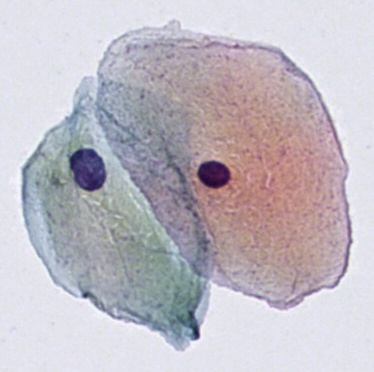

细胞实例分割数据集

数据集下载链接:http://suo.nz/3bokV6

引入了新的大型细胞实例分割数据集 (CISD)。它包括3911个样品,其中包含至少两个接触或重叠的尿路上皮细胞。细胞实例由训练有素的细胞技术人员手动注释。所有样品均从 30 张数字细胞学载玻片中提取,这些载玻片用 9 种不同的 Papanicolaou 染色染色。细胞学载玻片使用豪洛捷 ThinPrep®5000 处理器从健康患者的尿液样本中制备,并常规使用安捷伦 Dako 盖染色仪®进行染色。最终使用具有21个焦平面的Hamamatsu NanoZoomer®S360对载玻片进行数字化,并以扫描仪自动对焦确定的最佳焦平面为中心。